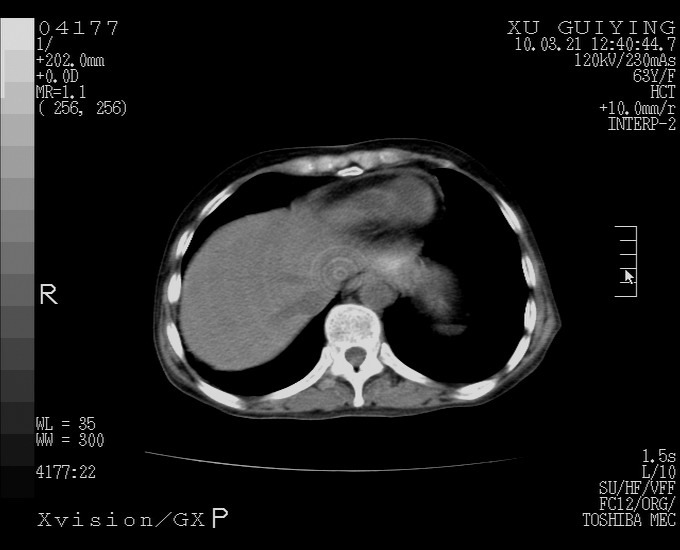

怎么没有增强呢?胆囊那么大,密度有些高啊。

慢性胆囊炎,胆囊占位不排除,建议增强或彩超。

考虑胆囊炎 不除外泥沙样结石

胆囊体积增大,胃窦壁增厚

胆囊体积增大

胆囊体积增大,密度不均匀,结石不除外;胃壁增厚,考虑胃癌,建议增强。

胆囊体积增大 ,建议超声检查。

胆囊体积增大,密度增高,较均匀,外缘也较光滑,应考虑胆囊炎。因为胃未充盈,不好说壁增厚。肝左叶及脾门处见低密度灶,有可能是血管瘤,不排除囊肿。建议超声检查或强化。

胆囊增大,原因待查。

这就是江湖人称的“内科黄疸”, 肝内胆汁淤积症(ic)?